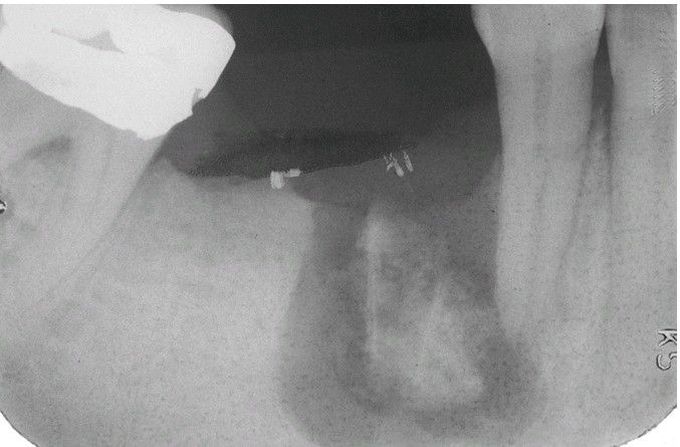

Acute Osteomyelitis with Sequestrum.

Radiolucency of the right body of the mandible with central radiopaque mass of necrotic bone